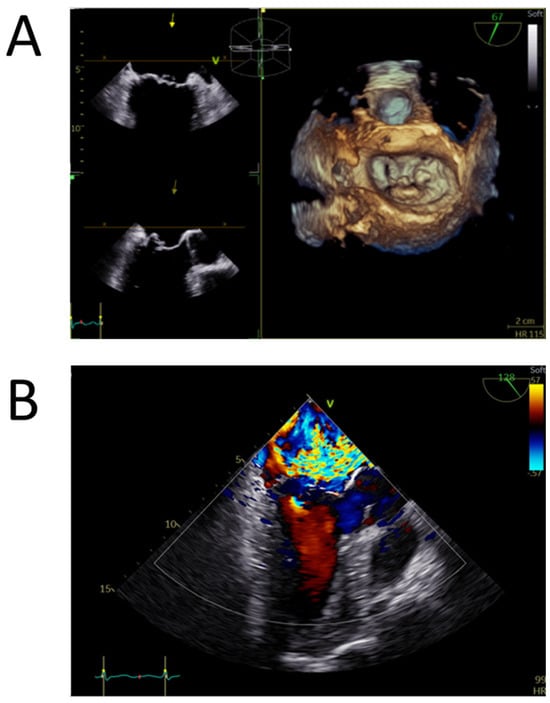

4.2. Preliminary Patient Evaluation